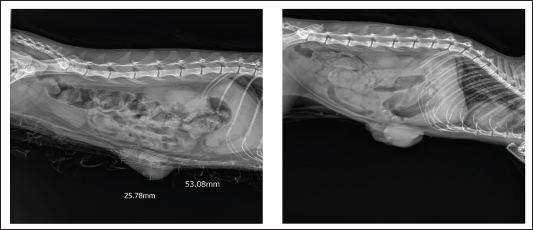

Serum progesterone and estradiol concentrations were compared between the affected and healthy control cats. Progesterone levels were markedly elevated in cats with FMH (16.27 ± 8.70 ng/ml) compared with normal controls (2.45 ± 1.78 ng/ml). Welch’s t-test (two-tailed) indicated that this difference was statistically significant (p=0.009, p < 0.01), demonstrating that the disease was associated with excessive luteal activity and pathological overproduction of progesterone. The mean serum estradiol concentration in affected cats (13.37 ± 3.23 pg/ml) was lower than that of healthy controls (28.33 ± 7.64 pg/ml). However, Welch’s t-test showed that this difference was not statistically significant (p=0.066). Therefore, estradiol cannot be confirmed or excluded as a contributing factor to FMH, and further studies with larger sample sizes are recommended. RadiographyOn radiography images, the mammary gland tissue shows enlargement of the mammary glands with intact body wall (Fig. 3).

Fig. 3. Radiography images of mammary gland tissue showing enlargement of the mammary glands with intact body wall in different affected female cats. UltrasonographyOn ultrasound images, mammary gland tissue showed higher echogenicity than normal tissue. The FMH lesions were well-defined, slightly hyperechoic, lobulated masses containing multiple small anechoic clefts within the mammary parenchyma. The intraductal pattern is dominant, with anechoic areas corresponding to clefts of different shapes within the mammary gland parenchyma. The presence of clefts in mammary fibroepithelial lesions provided a more heterogeneous appearance to the ultrasound images (Fig. 4). In the solid lesions, the ultrasound pattern is more homogeneous (Fig. 5).